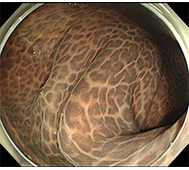

食道がん

日本では、60歳代の男性に好発し、男女比は、3:1程度です。 そのほとんどが扁平上皮癌で、発生部位は胸部中部食道に多くみられます。 原因として飲酒と喫煙があげられます。